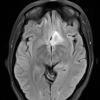

NEOPLASMS (GLIAL)

Astrocytoma, IDH-mutant, WHO Grade 2 (7)